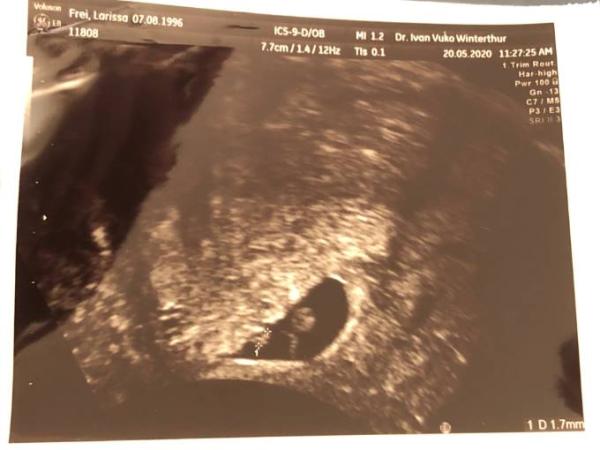

, bei dem anderen (1.7mm) schlägt es zu langsam. Er hat mir gesagt, dass dies ein Anzeichen sein kann, dass sich der Embryo nicht richtig entwickelt (und dementsprechend verloren geht), muss aber nicht. Er teilte mir auch mit, dass er selbst dies bei einer Zwillingsschwangerschaft nicht erlebt hat (ich versäumte ihn zu fragen ob er es denn schon erlebt hat, dass das eine Herz nicht schlug) und, dass er bei "einlingsss" nichts sagt, wenn das Herz zu langsam ist, da es viele Frauen verunsichert und die sich Sorgen machten und dann beim nächsten Termin alles in Ordnung ist. Da ich aber beide Herze gesehen hab, teile er es mir mit, da ich den Unterschied ja selbst sehen konnte. Er meinte auch, dass es möglich ist, dass man beim kleineren das Herz nicht so gut sieht, weil es zu klein resp. einfach kleiner als das andere ist. Den nächstem Termin habe ich am Freitag in einer Woche.

hier das kleinere